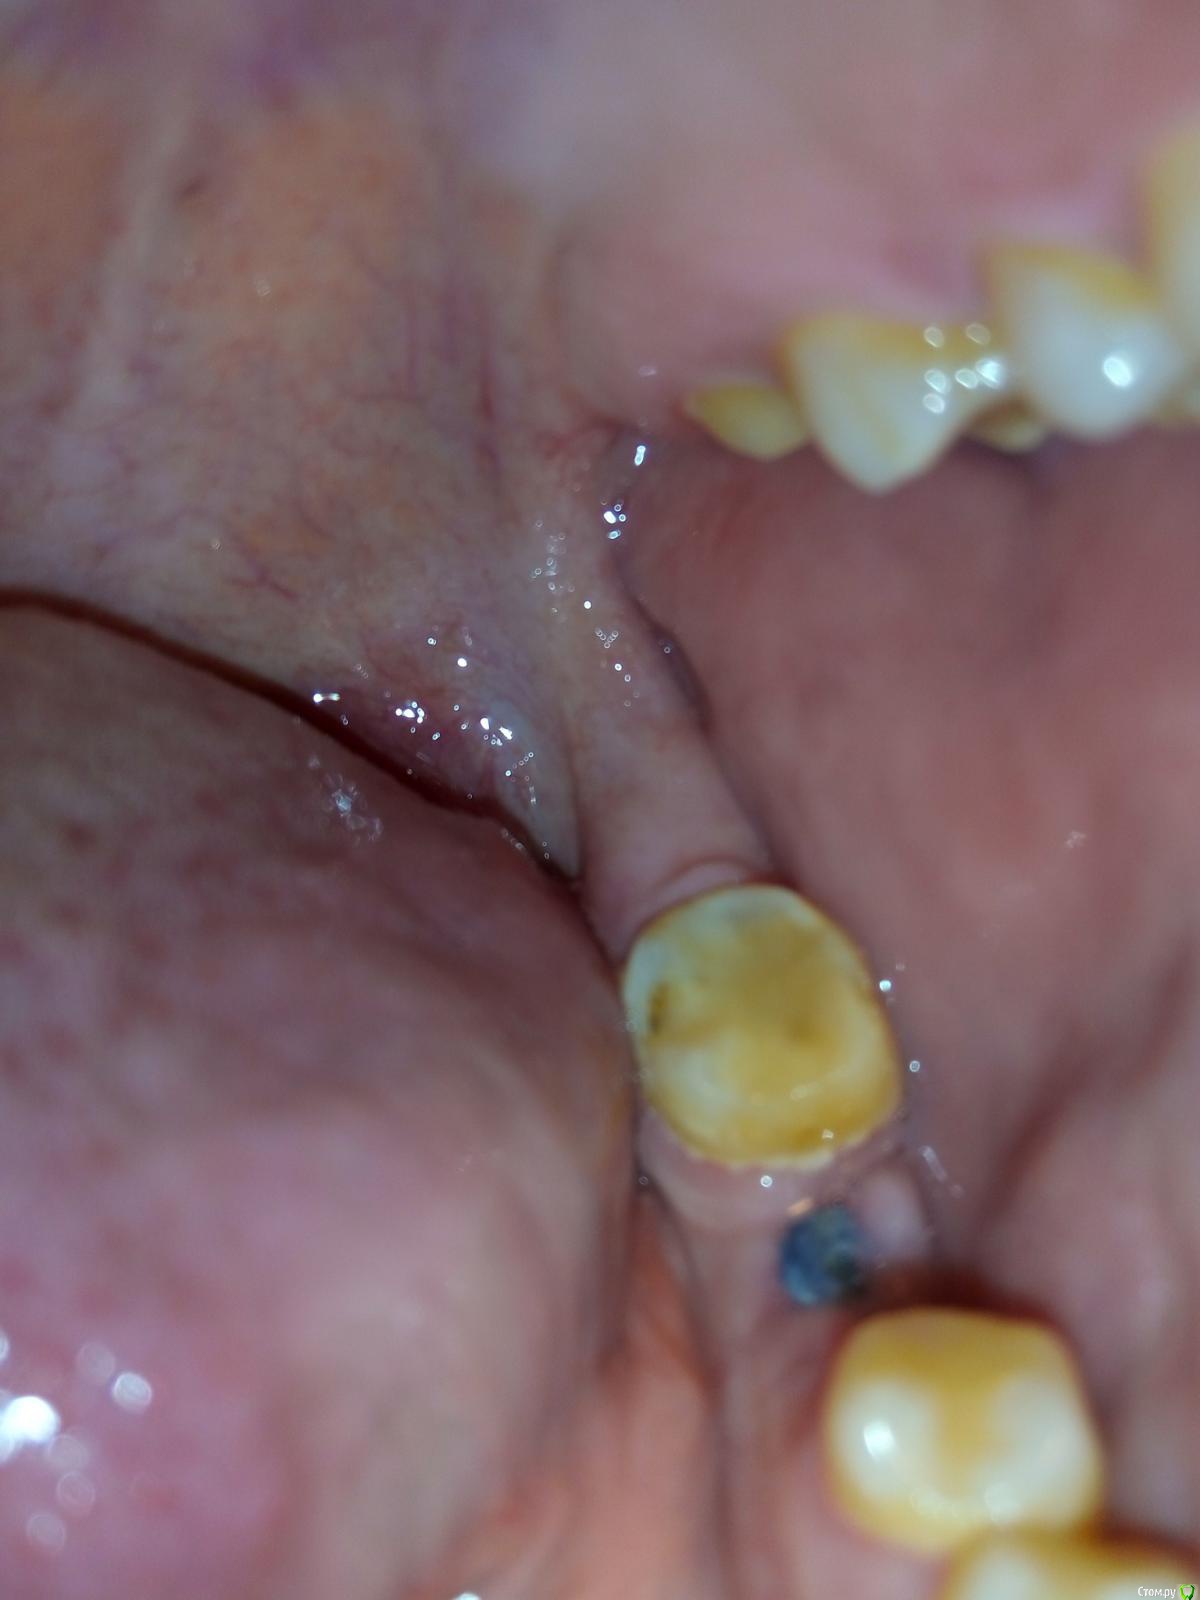

Katyanya Опубликовано 5 января, 2016 Поделиться Опубликовано 5 января, 2016 здравствуйте, нахожусь в другом городе, к зубному через 2 недели. Неделю назад сняли швы, виден имплант. Мне грозит еще раз наложение швов? Чем сейчас мазать чтоб десна быстрее сошлась? Спасибо Ссылка на комментарий

Katyanya Опубликовано 5 января, 2016 Автор Поделиться Опубликовано 5 января, 2016 (изменено) Часть десны со стороны щеки закрывает имплант а другая часть десны открыта Изменено 5 января, 2016 пользователем Katyanya Ссылка на комментарий